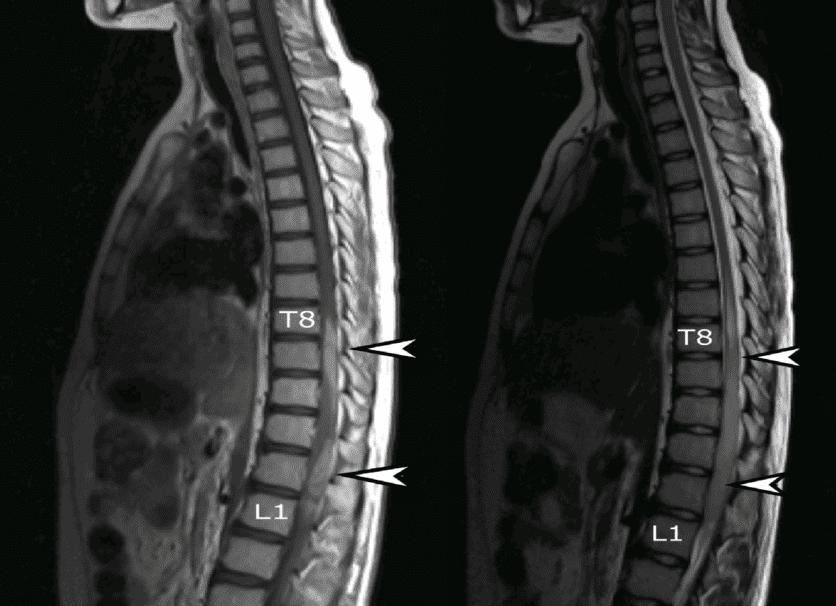

Межпозвоно́чная грыжа (межпозвонко́вая грыжа, грыжа межпозвоночного диска) — это смещение пульпозного ядра межпозвоночного диска с разрывом фиброзного кольца. Наиболее часто встречаются грыжи межпозвонковых дисков пояснично-крестцового отдела позвоночника (150 случаев на 100 000 населения в год), значительно реже наблюдаются грыжи в шейном отделе позвоночника, наиболее редки — в грудном отделе. Хотя грыжи относительно редко требуют хирургического вмешательства, тем не менее в США ежегодно проводится более 200 тысяч, а Германии 20 тысяч вмешательств. В 48 % случаев грыжи локализуются на уровне L5-S1 пояснично-крестцового отдела, в 46 % случаев — на уровне L4-L5, остальные 6 % на других уровнях или на нескольких уровнях пояснично-крестцового отдела.